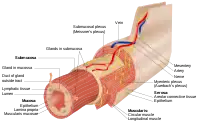

| This article is one of a series on the |

| Gastrointestinal wall |

The mucosa is composed of one or more layers of epithelial cells that secrete mucus, and an underlying lamina propria of loose connective tissue.[1] The type of cells and type of mucus secreted vary from organ to organ and each can differ along a given tract.[2][3]

Mucous membranes line the digestive, respiratory and reproductive tracts and are the primary barrier between the external world and the interior of the body; in an adult human the total surface area of the mucosa is about 400 square meters while the surface area of the skin is about 2 square meters.[4]: 1 Along with providing a physical barrier, they also contain key parts of the immune system and serve as the interface between the body proper and the microbiome.[2]: 437